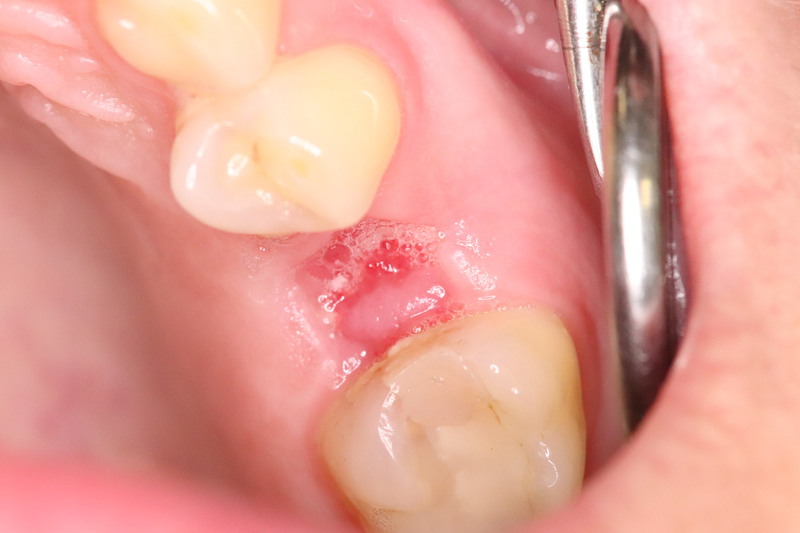

Oberkiefer 25

Entfernung des Zahnes 25, DentOss grob, 1Tag, 2,4 und 7 Wochen danach, Rö Kontrollen. Implantat 3 Monate nach Socket. RÖ Kontrolle 2 Jahre nach Socket.